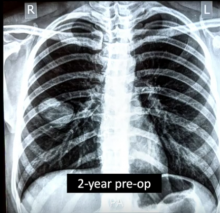

The patient was an otherwise healthy 26-year-old woman who presented with shortness of breath and chest pain. The patient was advised to quarantine based on suspicion of COVID-19. A week later, the patient presented to the emergency department with a pleural effusion and hemoptysis. She had an ultrasound of the pleural space and then a small-bore chest tube was inserted. The patient had CT and was diagnosed with a ruptured pulmonary hydatid cyst. The patient subsequently had two chest tubes inserted and three doses of intrapleural fibrinolytic therapy. She was then taken to the operating room for surgical management. Postoperatively, the patient had three chest tubes. The chest tubes were removed sequentially and she was discharged home on postoperative day 12. The patient had no intra-operative or postoperative complications.